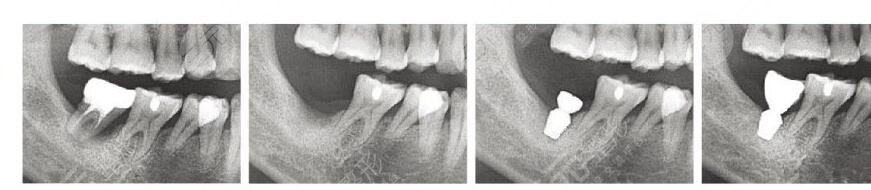

韩国登腾种植牙多少钱一颗2023?牙齿种植技术比较受欢迎,而且也是比较常见的修复牙齿的一种方式,主要是通过植入种植体然后再做烤瓷冠修复,这样就完成了种植牙种植牙体系分为很多韩国种植牙就比较受欢迎。韩国登腾种植牙是使用率比较高的,而且范围也比较广泛,但是关于价格的问题很多人不清楚。那么:韩国登腾种植牙多少钱一颗?其实在选择韩国登腾种植牙体系之前,关于价格的问题也是应该了解的话题。

韩国登腾种植牙,采用的是四级纯钛的材质,植体表面采用的是S.L.A处理技术。登腾种植牙,表面也能够有效提高初期的稳定性,而且能够跟牙槽骨紧密的结合在一起,缩短了牙齿种植的时间。韩国登腾种植牙主要是为黄皮肤的人群进行设计,能够带来更加坚固稳定的效果。